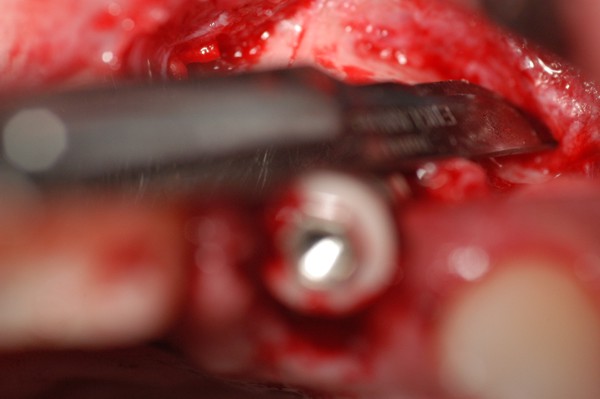

Abstract: Las fuerzas anterógradas traumáticas son en general las causantes de fracturas radiculares en el sector anterior de la boca. Desarrollo: El paciente se presenta a la consulta , con la fractura de una funda de porcelana inyectada en la zona cérvico palatina, solicitando simplemente la reparación en boca para evitar rozamientos linguales. Dicha funda con un perno colado en oro y su correspondiente endodoncia, habían sido realizadas en mi clínica varios años atrás, con un «aparente éxito total». Radiograficamente, se encuentra una fractura radicular cercana al tercio gingival Observada la oclusión de las piezas anteriores, podemos ver que el vínculo ideal de Acoplamiento, no se cumple, habiendo una relación de franco contacto la que ha provocado la fractura. Llevando al paciente a Oclusión en Relación Céntrica, podemos ver el espacio a nivel anterior, correspondiente a la centricidad mandibular. En esa misma posición , es dable percibir una faceta parafuncional mesial del primer premolar superior… …que antagoniza con una faceta parafuncional distal del canino inferior… ..constituyendo un plano inclinado que provoca la antelación mandibular o Discrepancia Horizontal, fracturando la raiz del incisivo central. Extraida la porción coronal de la raiz, pensamos en la realización de un Implante Inmediato, a pesar de la presencia de una fístula dado que se trataba de un central, decisión que obtuvo éxito implantario mas no estético, según veremos luego. Era fundamental conservar lo mas posible las tablas óseas, que de hecho había perdido la porción cervical Realizamos una incisión que conservara las papilas de las piezas adyacentes. Realizamos la exodoncia mediante un instrumento construido «ad hoc» que denomino: Con lo que obtenemos la preservación «ad integrum» de las corticales peridentarias remanentes. Instalamos entonces un implante T.B.R. de 15 mm de largo por 4 mm de diam. con cuello de zirconio de 3,5 mm …quedando tres espiras sin hueso por vestibular, producto de la tabla perdida, Incidimos el periostio a nivel apical del colgajo para obtener mayor paño quirúrgico, y legramos un bolsillo palatino sin incisiones de descarga, para la inserción de la membrana. Suplementamos la carencia ósea vestibular con «BIOSS» …e instalamos una membrana reabsorbible «BIOGUIDE» , que fijamos con el mismo implante, y calzamos por palatino. Suturamos Instalamos nuestra provisional previamente confeccionada, sobre un abuttment de titanio. Y controlamos radiograficamente Pasadas tres semanas del retiro de los puntos, observamos una cicatrización alta que nos muestra el anillo de zirconio del implante. ……………………………………………….. Transcurridos tres meses preparamos una nueva cirugía, dirigida a instalar un injerto autólogo de conectivo en el área del anillo, con un nuevo desplazamiento del colgajo vestibular. Tomamos tejido conectivo del paladar a nivel de los premolares, mediante una incisión mucosa «en libro», y disección del conectivo subyacente. Lo posicionamos en vestibular del anillo de zirconio y lo fijamos mediante sutura Y semanas después nos encontramos con un nuevo fracaso de orden estético. ……………………………………………….. En la actualidad, el caso esta estable , aún con su funda provisional, a la espera de un nuevo intento plástico, mediante Injerto Libre de Encia. ………………………………………………….. ESQUEMA MECÁNICO DEL FENÓMENO …que además de los hechos mostrados en el caso presentado, frecuentemente provocan en el sentido antero posterior los fenómenos de DISPERSIÓN ,en el maxilar superior…y de APIÑAMIENTO en el maxilar inferior. CONCLUSIONES: Además del rigor académico que nos convoca… esta; nuestra casa…nos otorga la confianza que solo da el saber que estamos siempre entre amigos, que cada vez son más. Por tanto es que debo decir: YO fui el responsable de dicha fractura… …porque… …..que hubiera sucedido si hubiera hecho todo el trabajo implantario sin ajustar previamente su oclusión? Seguramente a esta altura del caso…también hubiera fracasado el implante. Siempre decimos que se aprende de los errores más que de los aciertos, y Dr. Carlos A. Acuña Priano

Fig.20(Pie de foto: Incisión del periostio)

Fig.21(Pie de foto: injerto aloplástico )